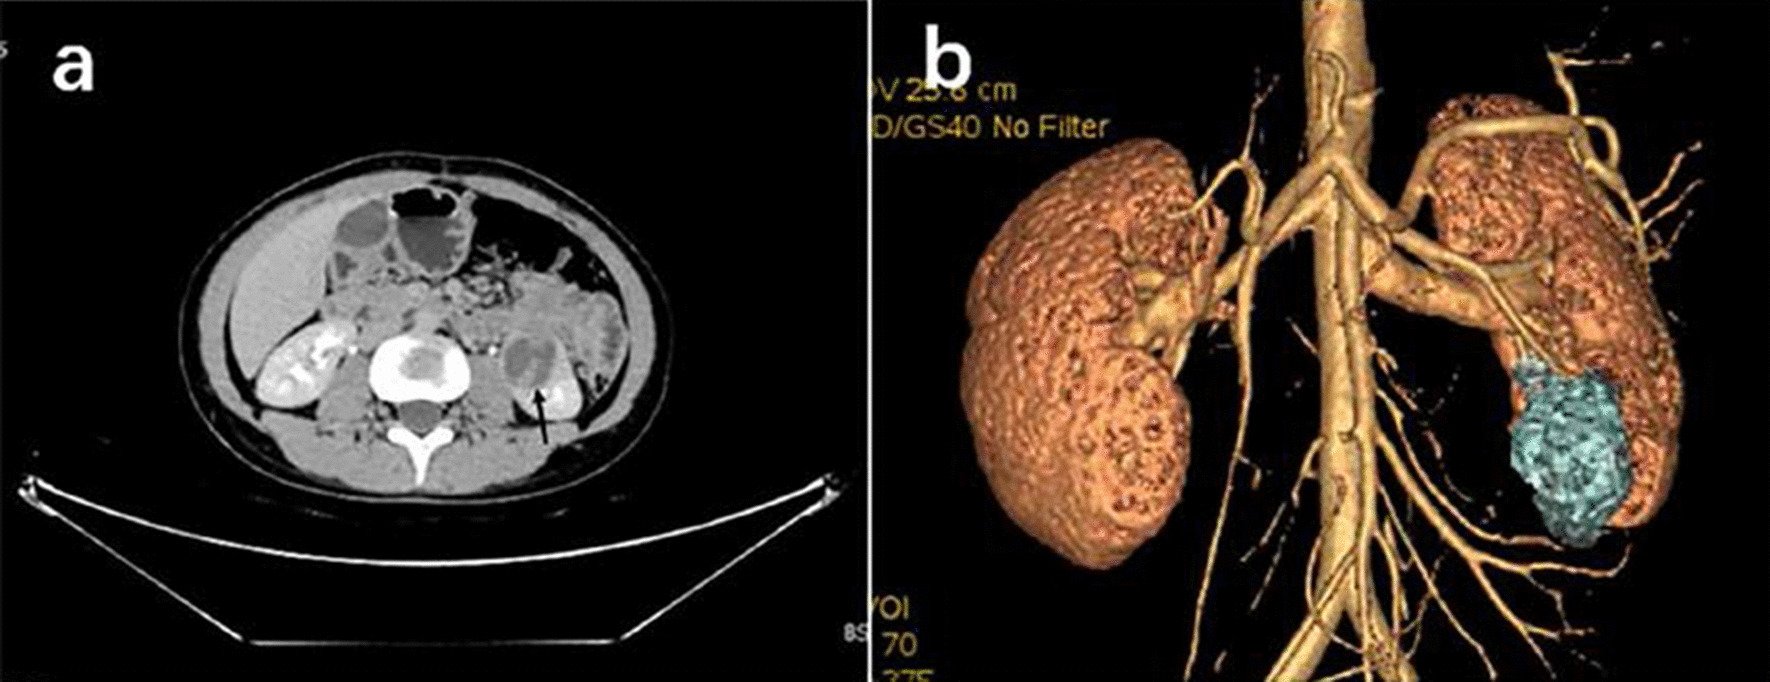

Fig. 2.

a Computerized tomography (CT)of the urinary system showed a heterogeneous mass in the left kidney(arrow). b Three-dimensional reconstruction of the kidney showed the lower 1/3 of the left kidney was occupied

A 20-year-old female presented to the hospital with an abdominal mass and gross haematuria for 1 month. She recently complained of left abdominal pain, nausea and vomiting, and noticeable weight loss. The patient did not have a family history of malignant tumours. The physical examination revealed abdominal distention with a large mass in the left upper quadrant. The mass was irregular, hard, immovable, nontender and without overlying skin changes. The laboratory test results for tumour markers were as follows: carbohydrate antigen 125 (CA-125), 136.89 U/mL (reference range: 0.00–35.00 U/ml); the levels of other tumour markers, such as carcinoembryonic antigen (CEA), carbohydrate antigen 199 (CA-199), and alpha-fetoprotein (AFP), were normal. Urine analysis showed that the red blood cell (RBC) count was 56/µl (reference range: 0.0–25.0), and the white blood cell (WBC) count was 59/µl (reference range: 0.0–25.0). Liver and kidney function test results and the complete blood count were within normal levels. Conventional ultrasound (US) examination showed a 4.5 × 3.2 cm irregular lesion at the lower pole of the left kidney. To further clarify the diagnosis of the tumour, contrast-enhanced ultrasound (CEUS) was performed, which presented signs of annular enhancement and heterogeneous enhancement of the tumour, and simultaneous wash-in was predominant. The possibility of a tumour lesion was considered (Fig. 1). A CT scan showed a 3.7 × 3.8 × 4.0 cm heterogeneous mass in the left kidney, which had blurry edges and a high-density dissepiment in the interior. Three-dimensional reconstruction of the kidney showed that the lower one-third of the left kidney was occupied (Fig. 2). Gross total removal of the tumour was achieved. The tumour was a 3.5 × 3 × 2.6 cm well-defined grey‒white nodular mass with necrosis (Fig. 3). Hematoxylin–eosin staining (HE) and immunohistochemistry (Leica DM4 B, DFC7000 T camera and LAS X software) were performed. Under the microscope, the tumour cells were small, round, short spindle-shaped, and densely arranged; Homer Wright rosettes were found; the cytoplasm of the tumour cells was sparse; and the nuclei were slightly enlarged and hyperchromatic. The tumour tissue was accompanied by extensive haemorrhage and necrosis. Immunohistochemistry showed the following: CD99 ( +), Vimentin ( +), EMA (−), CD10 (−), CD56 (−), syn (−), and NSE (−) (Fig. 4). Other immunohistochemistry staining see supplementary information (Additional file 1). The pathological diagnosis was an EWS/pPNET that did not invade the ureters. Subsequently, 21 days after the operation, the patient received 8 cycles of a CAV (vinorelbine, ifosfamide, epirubicin) + IE (isocyclophosphamide, etoposide) regimen from December 1, 2017, to May 11, 2018. Adjuvant radiotherapy (dose: 45 Gy, radiation field: the tumour bed following surgical resection) was also administered from June 11, 2018, to July 13, 2018. At the same time, the serum CA-125 level of the patient showed a gradual downwards trend after surgery and chemotherapy. The serum CA-125 levels returned to normal at the end of chemotherapy and radiotherapy. The patient had no signs of local recurrence or metastasis on CT scan within a follow-up of 4 years.

Imaging methods, such as CT and MRI, have their own specific indications [14] to can help make a correct diagnosis [15]. The EWS/pPNET of the kidney was an inhomogeneous mass with unobvious renal vessels, no signs of invasion, and no calcifications on CT [16, 17]. In a 60-year-old patient with an EWS/pPNET of the kidney, ultrasound revealed an exophytic cortical cyst of the left kidney with irregular echogenic septa. Abdominal MRI and CT scans revealed a large lesion with necrosis of the mass. MRI showed homogeneous hypointensity on T1-weighted images and hyperintensity on T2-weighted images [18]. According to previous literature reports [19–23], we concluded that the CT characteristics of an EWS/pPNET of the kidney are as follows: (1) a large soft tissue mass, (2) the mass can be well defined, (3) necrosis can be found, (4) the renal vein or inferior vena cava may be involved, and (5) calcification is rare. Areas of high density correspond to areas of internal haemorrhage, and areas of low density correspond to areas of necrosis. The CT findings of the patient whose case is presented here are consistent with those previously reported [16–23]. As a radiation-free, inexpensive, and convenient examination method, US can be the primary choice in the diagnosis of EWS/pPNETs. Conventional US may fail to differentiate cystic and necrotic areas due to factors such as resolution. However, CEUS can solve this problem. The EWS/pPNET of the kidney mainly manifested as annular enhancement and heterogeneous enhancement on CEUS, and simultaneous wash-in was predominant in the EWS/pPNET of the kidney. Other common renal malignancies, such as clear cell renal cell carcinomas (ccRCCs), papillary renal cell carcinomas (pRCCs), and chromophobe renal cell carcinomas (chRCCs), can be differentiated from EWS/pPNETs of the kidney on CEUS. ccRCCs are rich in blood vessels, and the vessels of ccRCCs are large, irregular and distorted, with arteriovenous fistulas, which lead to the characteristics of early wash-in and hyperenhancement on CEUS [24]. Furthermore, the rapid tumour growth and proneness to ischaemic necrosis of ccRCCs lead to heterogeneous enhancement. In contrast, pRCCs and chRCCs, owing to the relative lack of vessels or the thick walls of vessels, often show hypoenhancement on CEUS. Previous studies [25] have reported that chRCCs mainly demonstrated simultaneous wash-in, while pRCCs mainly demonstrated slow wash-in. For the wash-out pattern, rapid wash-out mostly appeared in pRCCs and chRCCs. Additionally, EWS/pPNETs need to be distinguished from other uncommon renal tumours, such as adult Wilms, tumours, rhabdoid tumours, and renal clear cell sarcomas. Preoperative diagnosis of these tumours is difficult because there are no specific radiographic findings, and diagnosis relies primarily on histopathology.